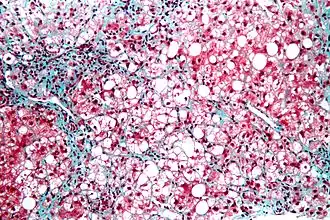

![]() Микрофотография стеатогепатита. Биопсия печени | |

Стеатогепатит — воспалительный процесс печени на фоне её жирового перерождения. Существует три вида заболевания: алкогольная болезнь печени, метаболический стеатогепатит и лекарственный стеатогепатит, которые нередко сочетаются между собой.